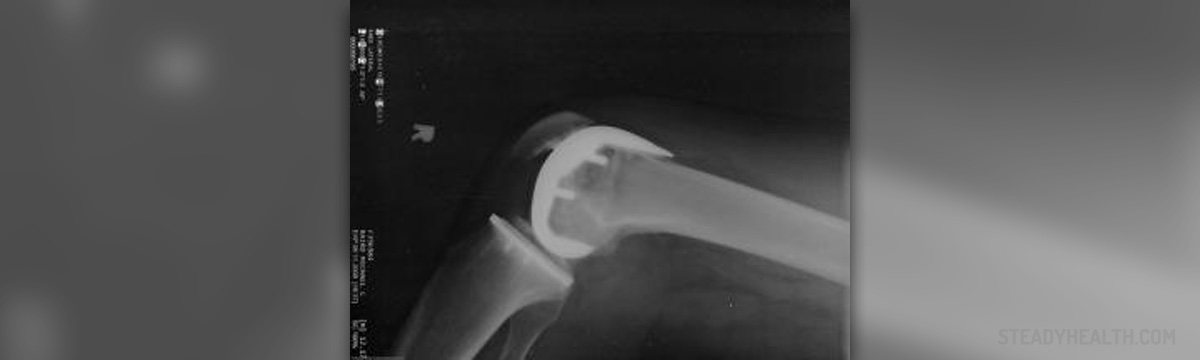

The treatment depends on the specific culprits that brought about this severe knee injury. Therefore, the best way to determine the precise cause, as well as the most proper treatment therapy is to pay a visit to a doctor who will put forward the appropriate diagnose by means of either an MRI scan or X-ray. In case dislocation has happened as a direct consequence of an injury, the first step is to immobilize the injured knee for a specific period of time, which means that a person in question will have to have the leg casted, in order to shield it from any additional injuries for the period of approximately 3 weeks. This will be followed by a physical therapy with the aim to enhance the overall strength of the muscles surrounding the knee. On the other hand, in case the dislocation has occurred as a direct consequence of the inability of the knee groove to hold the knee firmly, then corrective surgery is the best way to ameliorate and stop the recurrence of the injury in question.